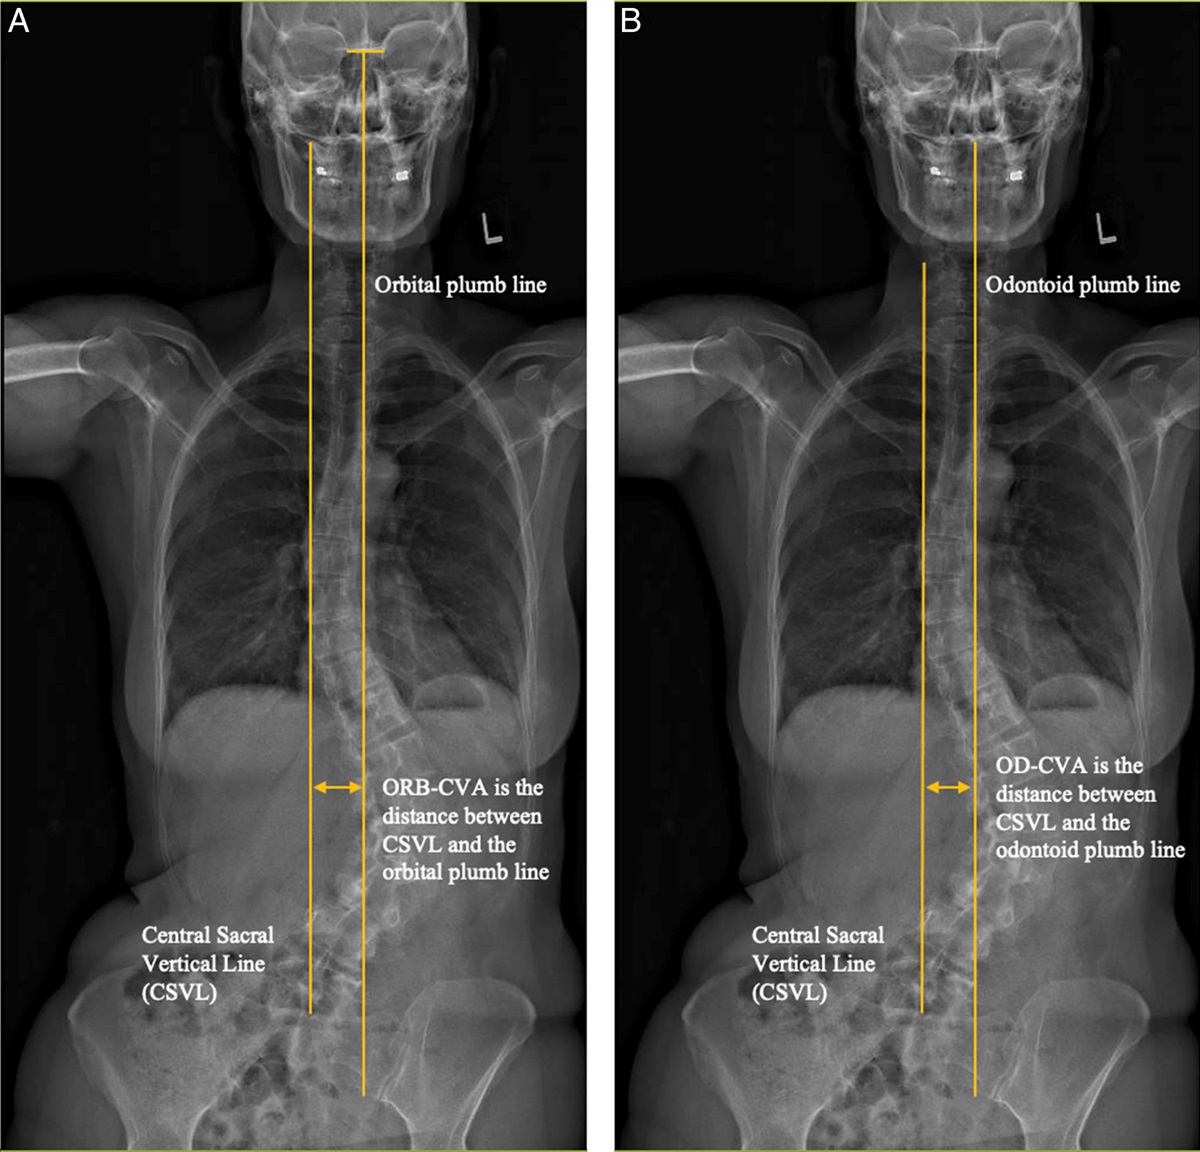

Current Issue: Comparison of the Odontoid and Orbital–Coronal Vertical Axis Lines in Evaluating Coronal Alignment and Outcomes in Adult Spinal Deformity Surgery https://t.co/HaBaf1FihE